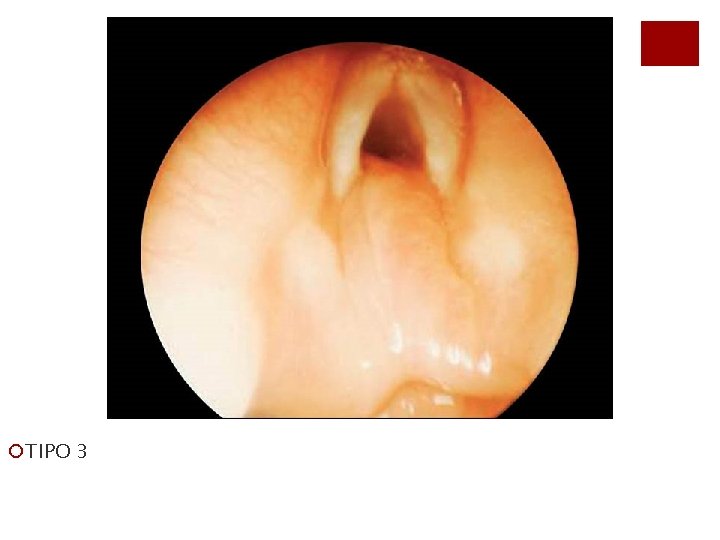

¡TIPO 3